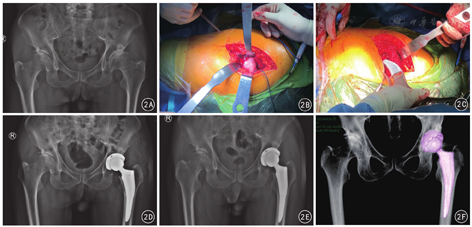

两组患者均未发生切口感染;对照组2髋因术中锉磨髓腔时出现股骨近端医源性骨折采取近端钢丝加固,观察组未见上述情况发生;对照组3例、观察组1例出现大腿远端疼痛。术后并发症总体发生率观察组(5.0%,1/20)低于对照组(25.0%,5/20),但差异无统计学意义(χ2 =1.765,P>0.05)。典型病例见图2。

(1)一般资料:比较两组患者性别、年龄及髓腔闪烁指数(canal flare index, CFI)等。(2)治疗效果:对患者术后第2日髋部疼痛改善情况进行VAS评估;术后12周使用Harris髋关节评分(harris hip score, HHS)标准评价患者髋部的整体功能,具体从疼痛、功能、髋关节活动和肢体畸形四个方面来评估,90~100分为优、80~89分较好,70~79分为尚可,<70分为差。(3)股骨假体位置及稳定性评估:参考Mulliken标准,术后即刻采用X线测量评估股骨假体置换后股骨柄的初始位置,以股骨柄居中或内外翻角度≤3°,同时股骨柄压配率于X线正位片达80%、侧位片达70%为股骨柄初始稳定性优良,未达此标准的为差。(4)双下肢绝对长度差:在手术前后双髋X线正位片上,分别测量双侧小转子基底部到坐骨结节连线的高度,记录两侧差值。(5)两组假体骨量保留参数比较:基于CT三维重建影像,于股骨小转子最宽部层面,测量股骨外层皮质、假体外层平面的面积,两者差值即为小转子最宽部骨量保留面积;应用Mimics 17.0软件重建并测量大转子最宽部至小转子最宽部容量体积,减去对应部位的假体体积,即为大小转子间骨量保留体积。见图1。(6)术中及术后早期并发症:股骨近端医源性骨折、大腿远端疼痛等。

观察组THA术后股骨柄初始稳定性优良率略高于对照组,差异无统计学意义(P>0.05)。两组患者双下肢绝对长度差术后较术前均有改善,差异均有统计学意义(P值均<0.01);但术前和术后组间比较,差异均无统计学意义(P值均>0.05)。观察组术后股骨小转子最宽部骨量保留面积、大小转子间骨量保留体积均优于对照组,差异均有统计学意义(P值均<0.01)。见表2。